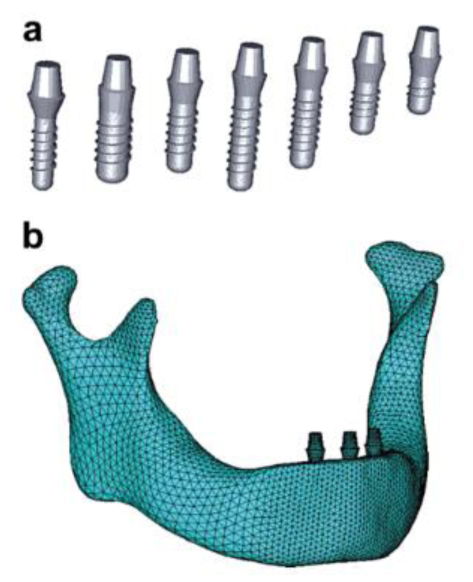

Special Issue 3: Special Issue Introduction on the Maxillofacial Rehabilitation: Biomaterials and

Techniques

Edited by: Dinesh Rokaya

September 01, 2021